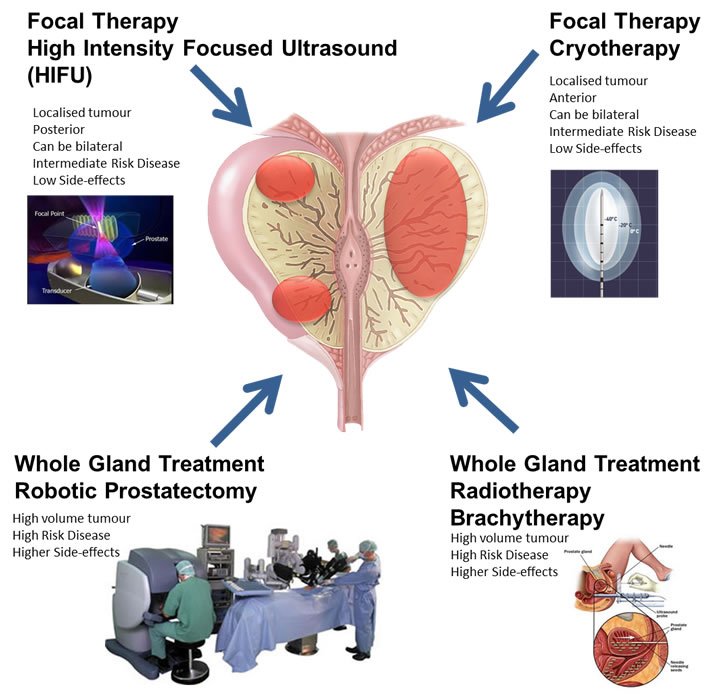

Prostate cancer – an overview of surgical treatments – Prostate Matters